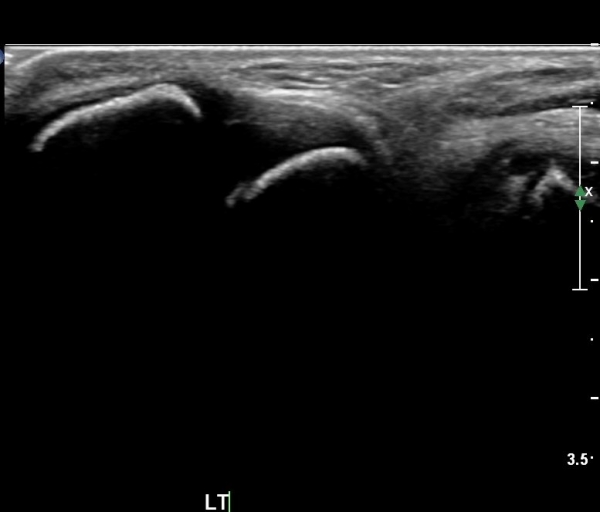

ÃÊÀ½ÆÄ °Ë»ç